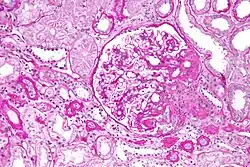

On histology, FSGS manifests as scarring (sclerosis) to segments of glomeruli; moreover, only a portion of glomeruli are affected.[7][20][21] The focal and segmental nature of disease seen on histology help to distinguish FSGS from other types of glomerular sclerosis.[21]

Diagnosis of FSGS is made by renal biopsy that includes at least fifteen serial cuts with at least eight glomeruli.[32][33] Histologic features include sclerosis (scarring) of a portion (average: 15%) of the glomerular space, with only a portion of glomeruli manifesting any sclerosis.[33]

Five mutually exclusive variants of focal segmental glomerulosclerosis may be distinguished by the pathologic findings seen on renal biopsy:[35]

- Collapsing variant

- Glomerular tip lesion variant

- Cellular variant

- Perihilar variant

- Not otherwise specified (NOS) variant

Recognition of these variants may have prognostic value in individuals with primary focal segmental glomerulosclerosis. The collapsing variant is associated with higher rate of progression to end-stage renal disease, whereas the glomerular tip lesion variant has a low rate of progression to end-stage renal disease in most patients.[9] The cellular variant shows similar clinical presentation to collapsing and glomerular tip variant but has intermediate outcomes between the other two variants.[9]